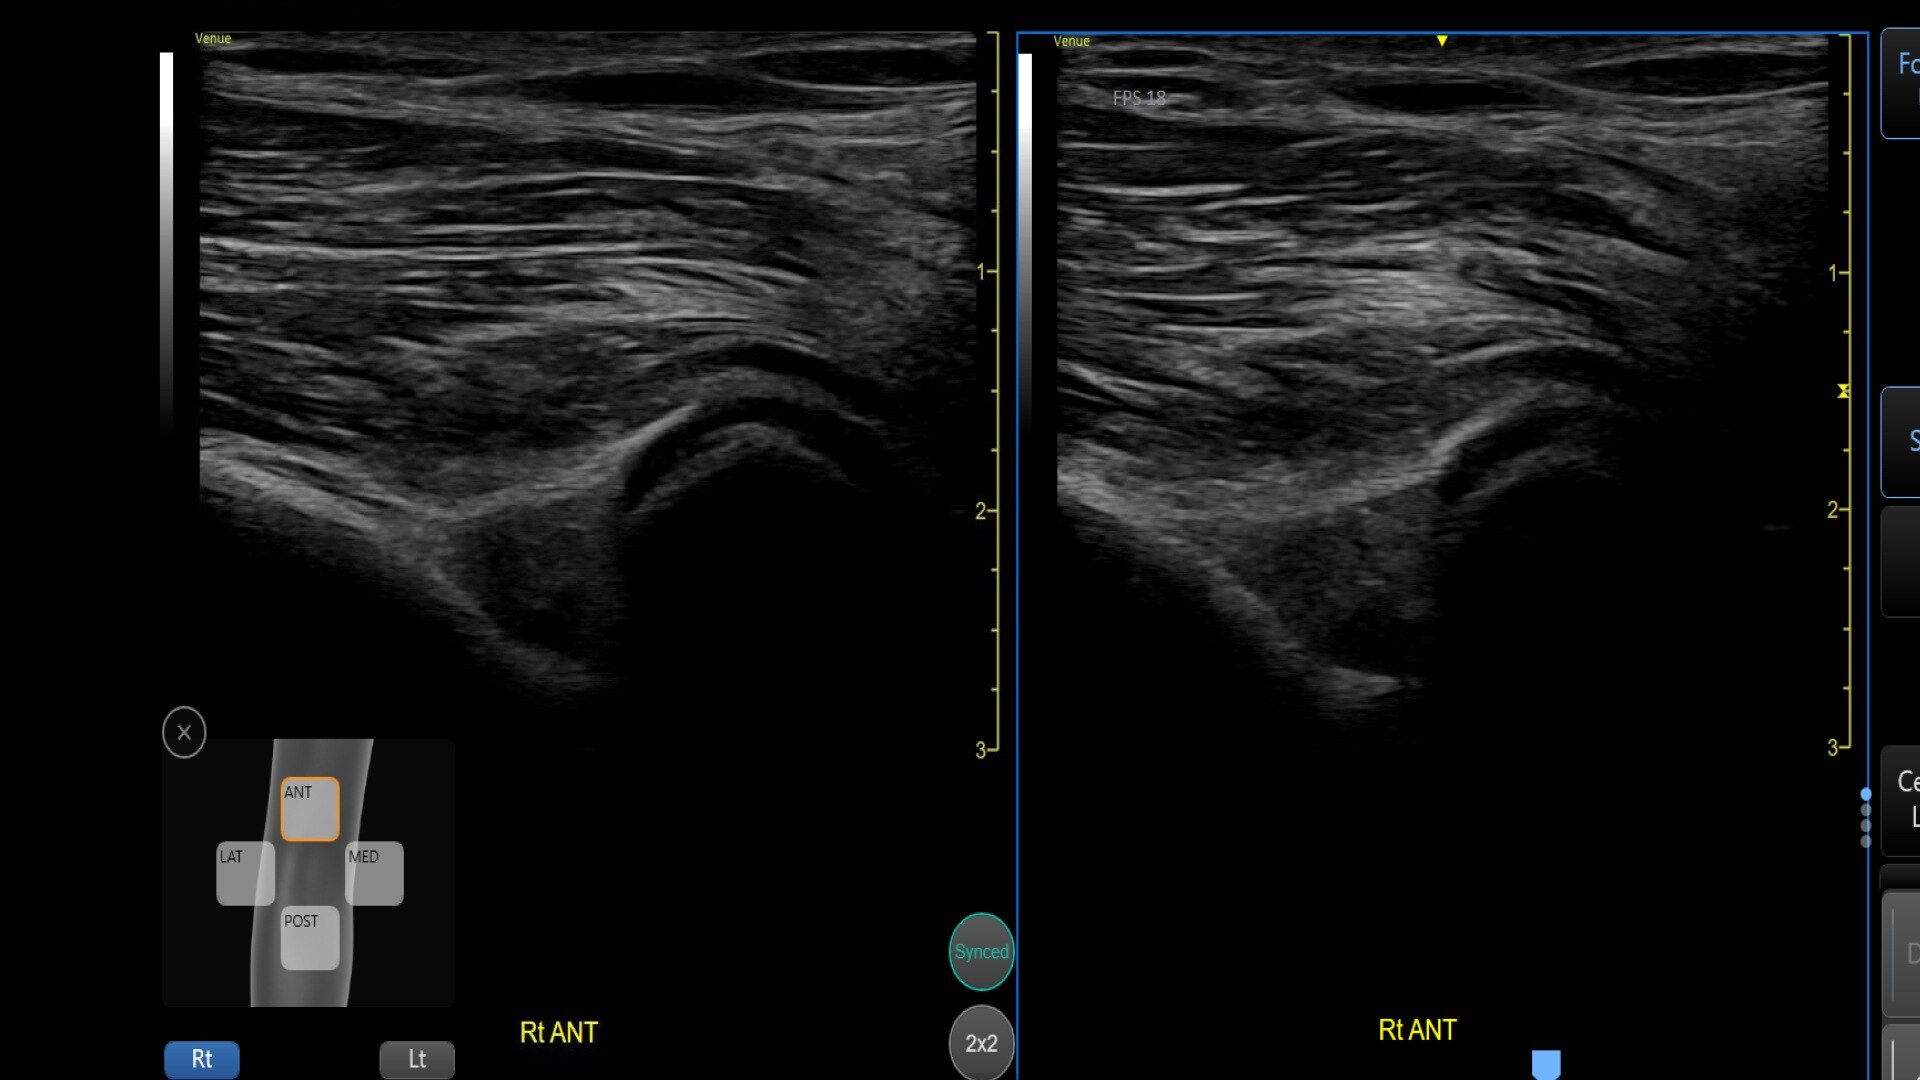

• Bilateral mode: Helps you to view the opposite side of the same zone for comparison (available for Shoulder preset)

Delivering consistent and clear conclusions for repeated exams on the same patient, Follow Up automatically recalls parameter settings from a previous exam including comments and body patterns. It also supports monitoring of patient response to treatment over time, allowing a side-by-side view of historical and new images.